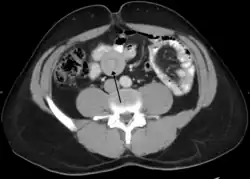

An intussusception as seen on CT | |

An intussusception is often suspected based on history and physical exam, including observation of Dance's sign. A digital rectal examination is particularly helpful in children, as part of the intussusceptum may be felt by the finger. A definite diagnosis often requires confirmation by diagnostic imaging modalities. Ultrasound is the imaging modality of choice for diagnosis and exclusion of intussusception, due to its high accuracy and lack of radiation. The appearance of target sign (also called "doughnut sign" on a sonograph, usually around 3 cm in diameter, confirms the diagnosis. The image seen on transverse sonography or computed tomography is that of a doughnut shape, created by the hyperechoic central core of bowel and mesentery surrounded by the hypoechoic outer edematous bowel.[10] In longitudinal imaging, intussusception resembles a sandwich.[10] It is also called "pseudokidney" sign because hyperechoic tubular centre is covered by a hypoechoic rim producing a kidney-like appearance.[11]